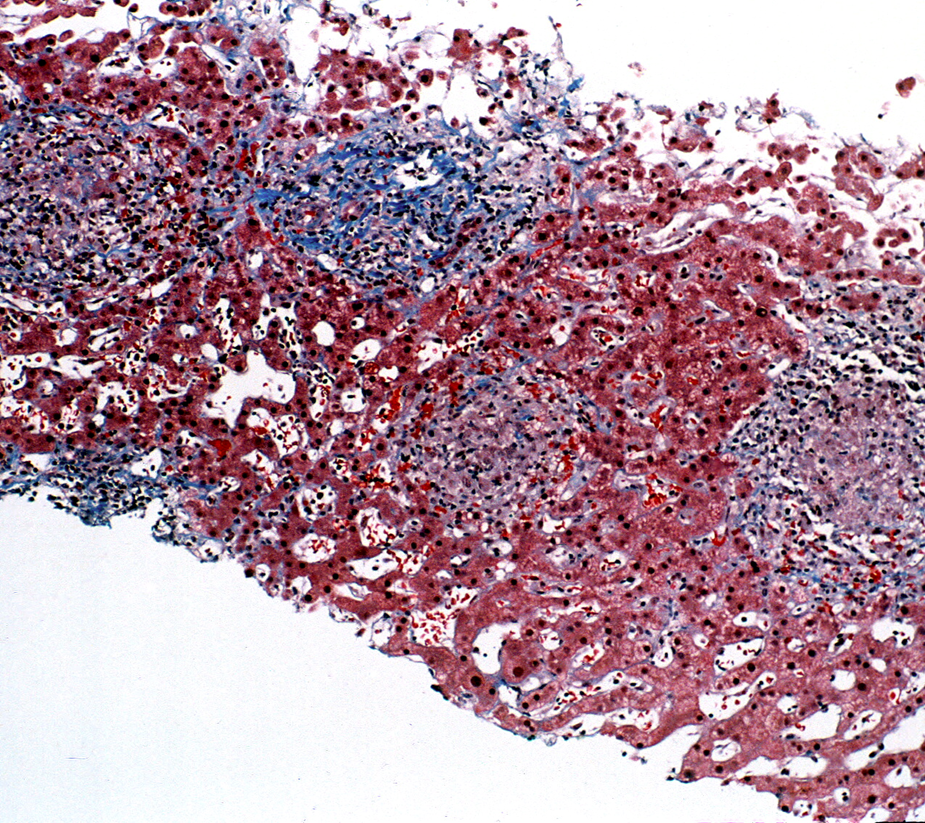

hepatic steatosis

steatohepatitis

steatohepatitis, pericellular fibrosis

steatohepatitis cirrhosis